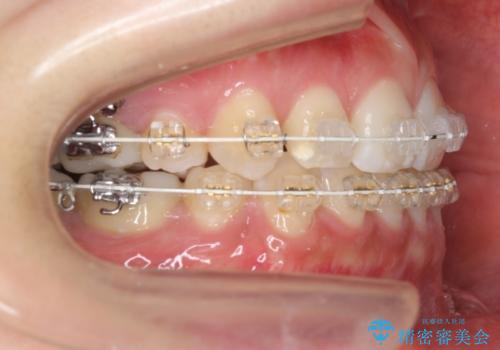

真ん中が右にずれている 前歯のがたつき 治療途中に地方へ引っ越したが、通ってワイヤー矯正

- 前歯のがたつきを主訴に来院。

前歯のクロスバイト、上の前歯の正中が右にずれていました。

右上の奥歯の高さもない状態でしたが、矯正治療が終わってからしっかりかぶせました。

上下左右の小臼歯を抜歯しています。

治療の後半に地方に転居され、2か月に一回の調整となり結果、治療期間がかかりました。

通院はしっかりしていただいたため、無事終了することができました。